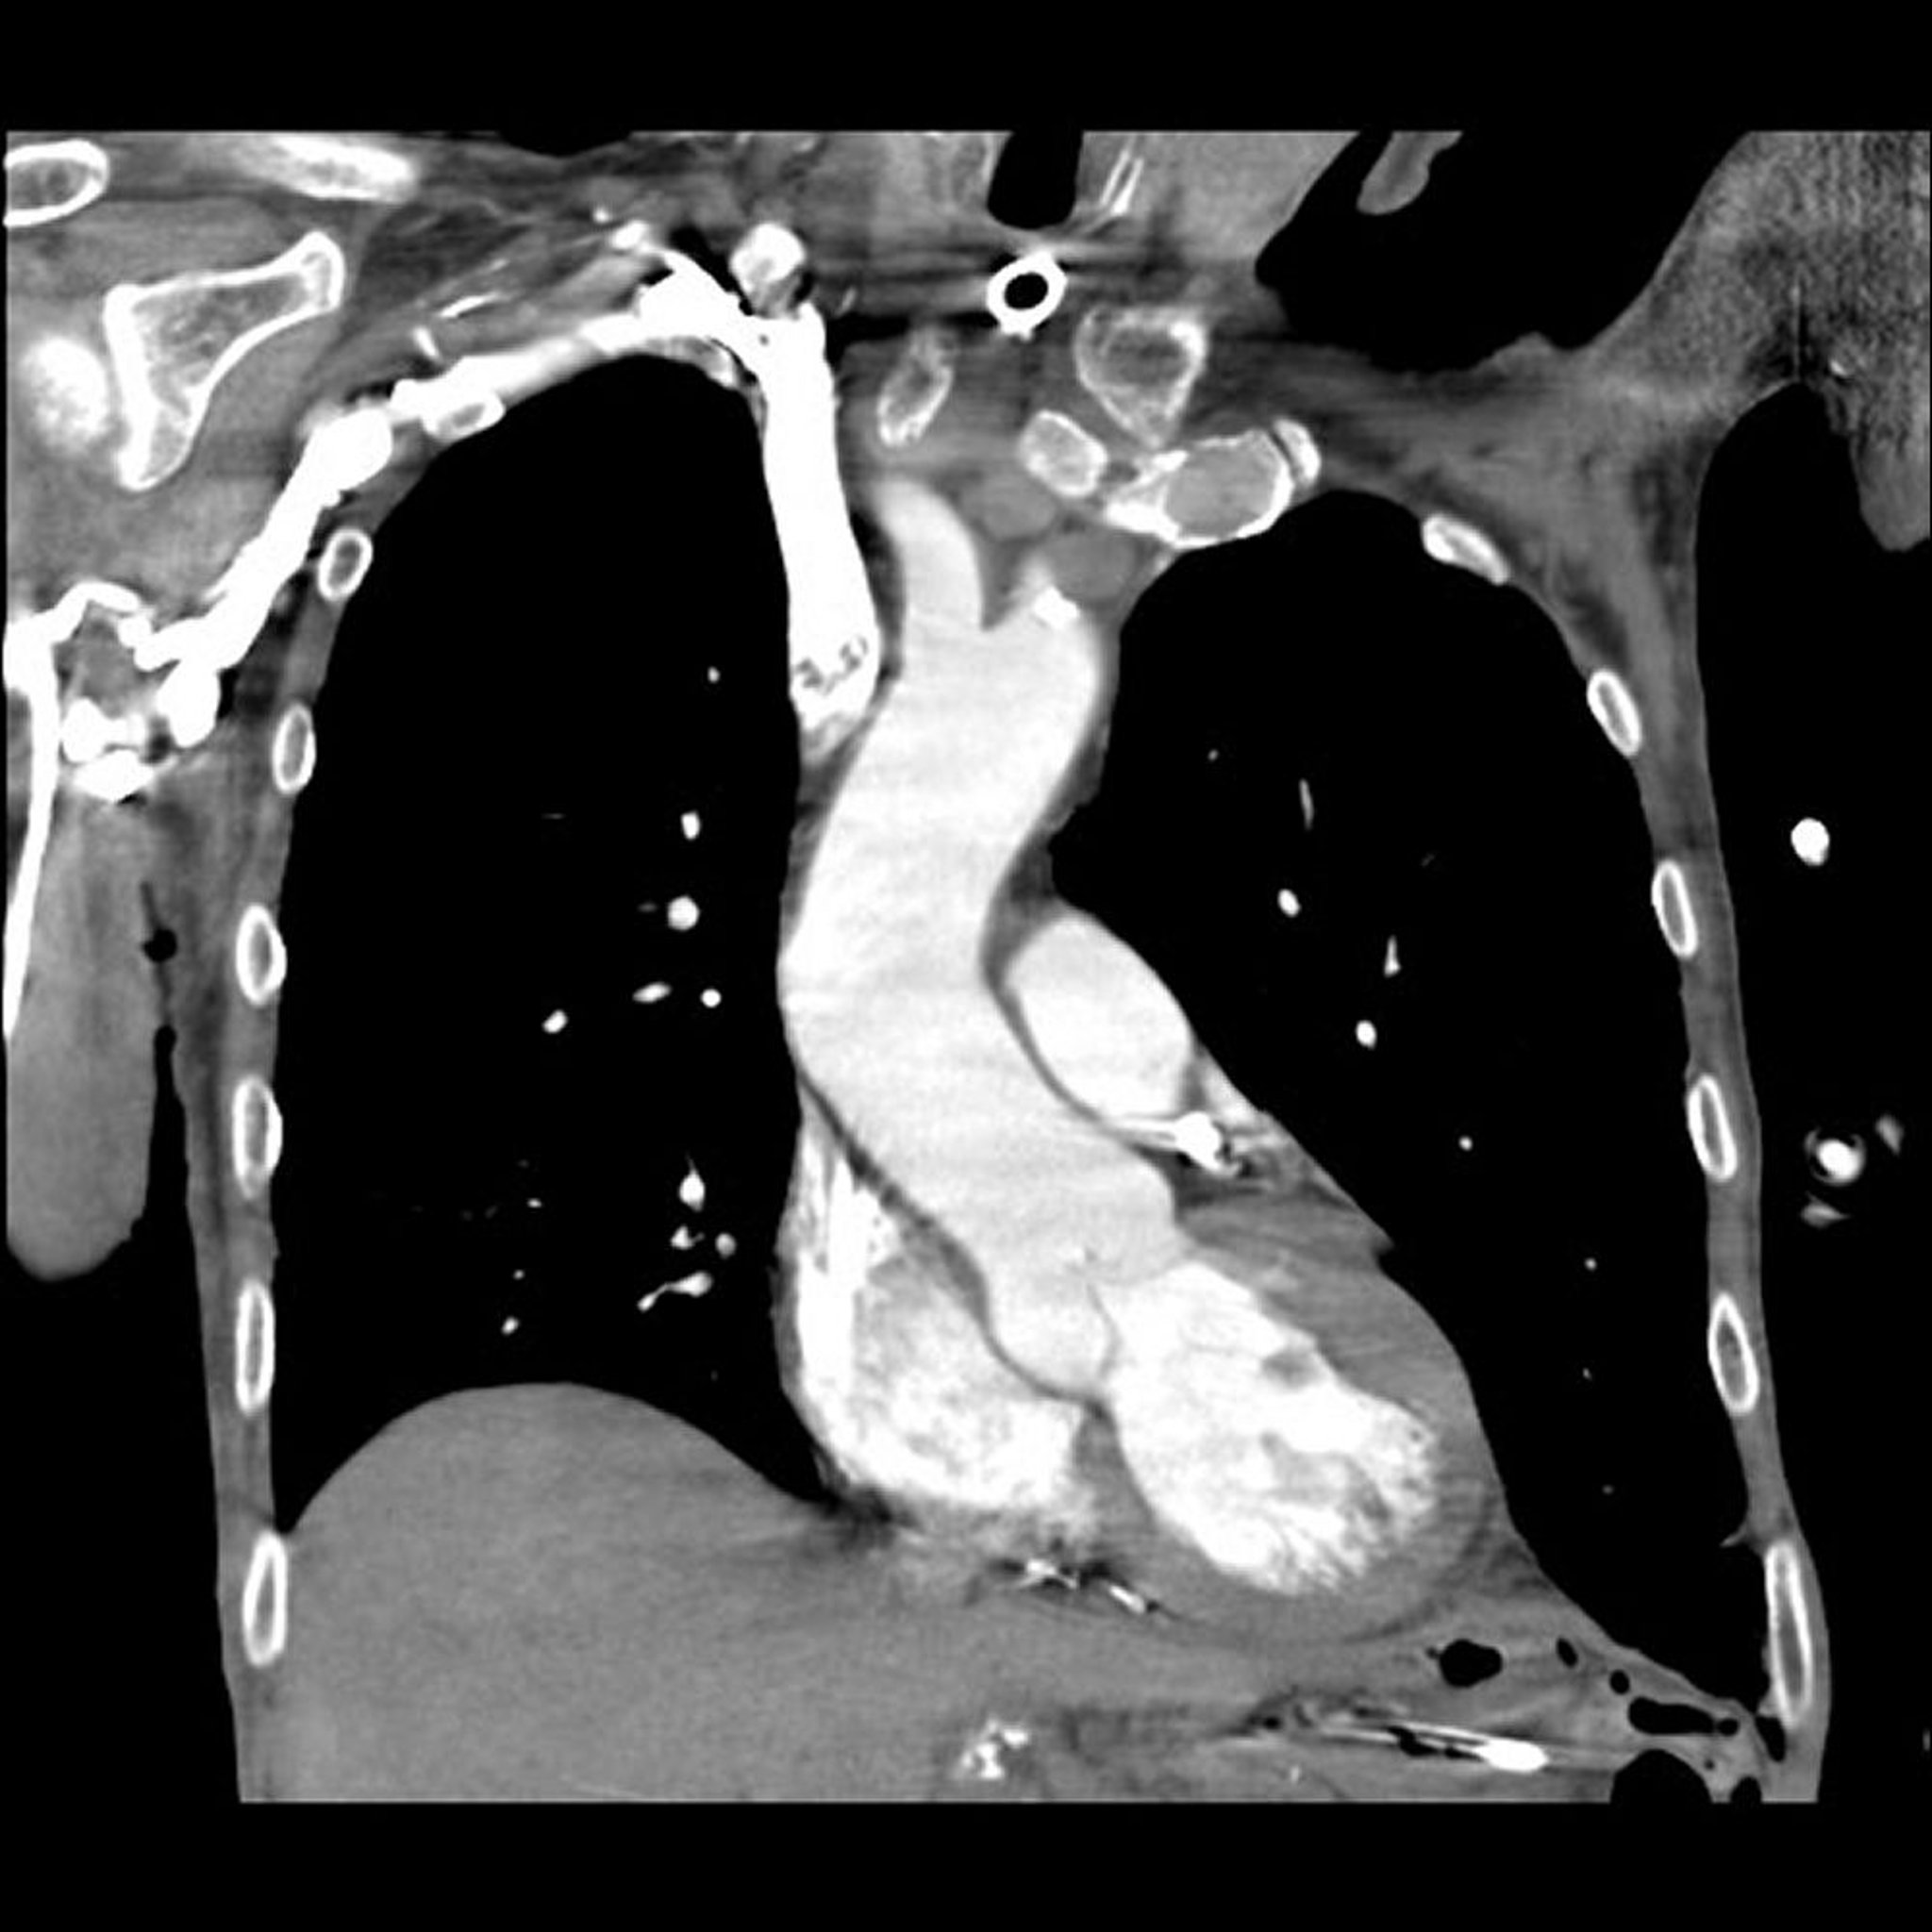

Angiografia polmonare con tomografia computerizzata (TC)

Immagine fornita dal Dott. Mehmet Kocak.